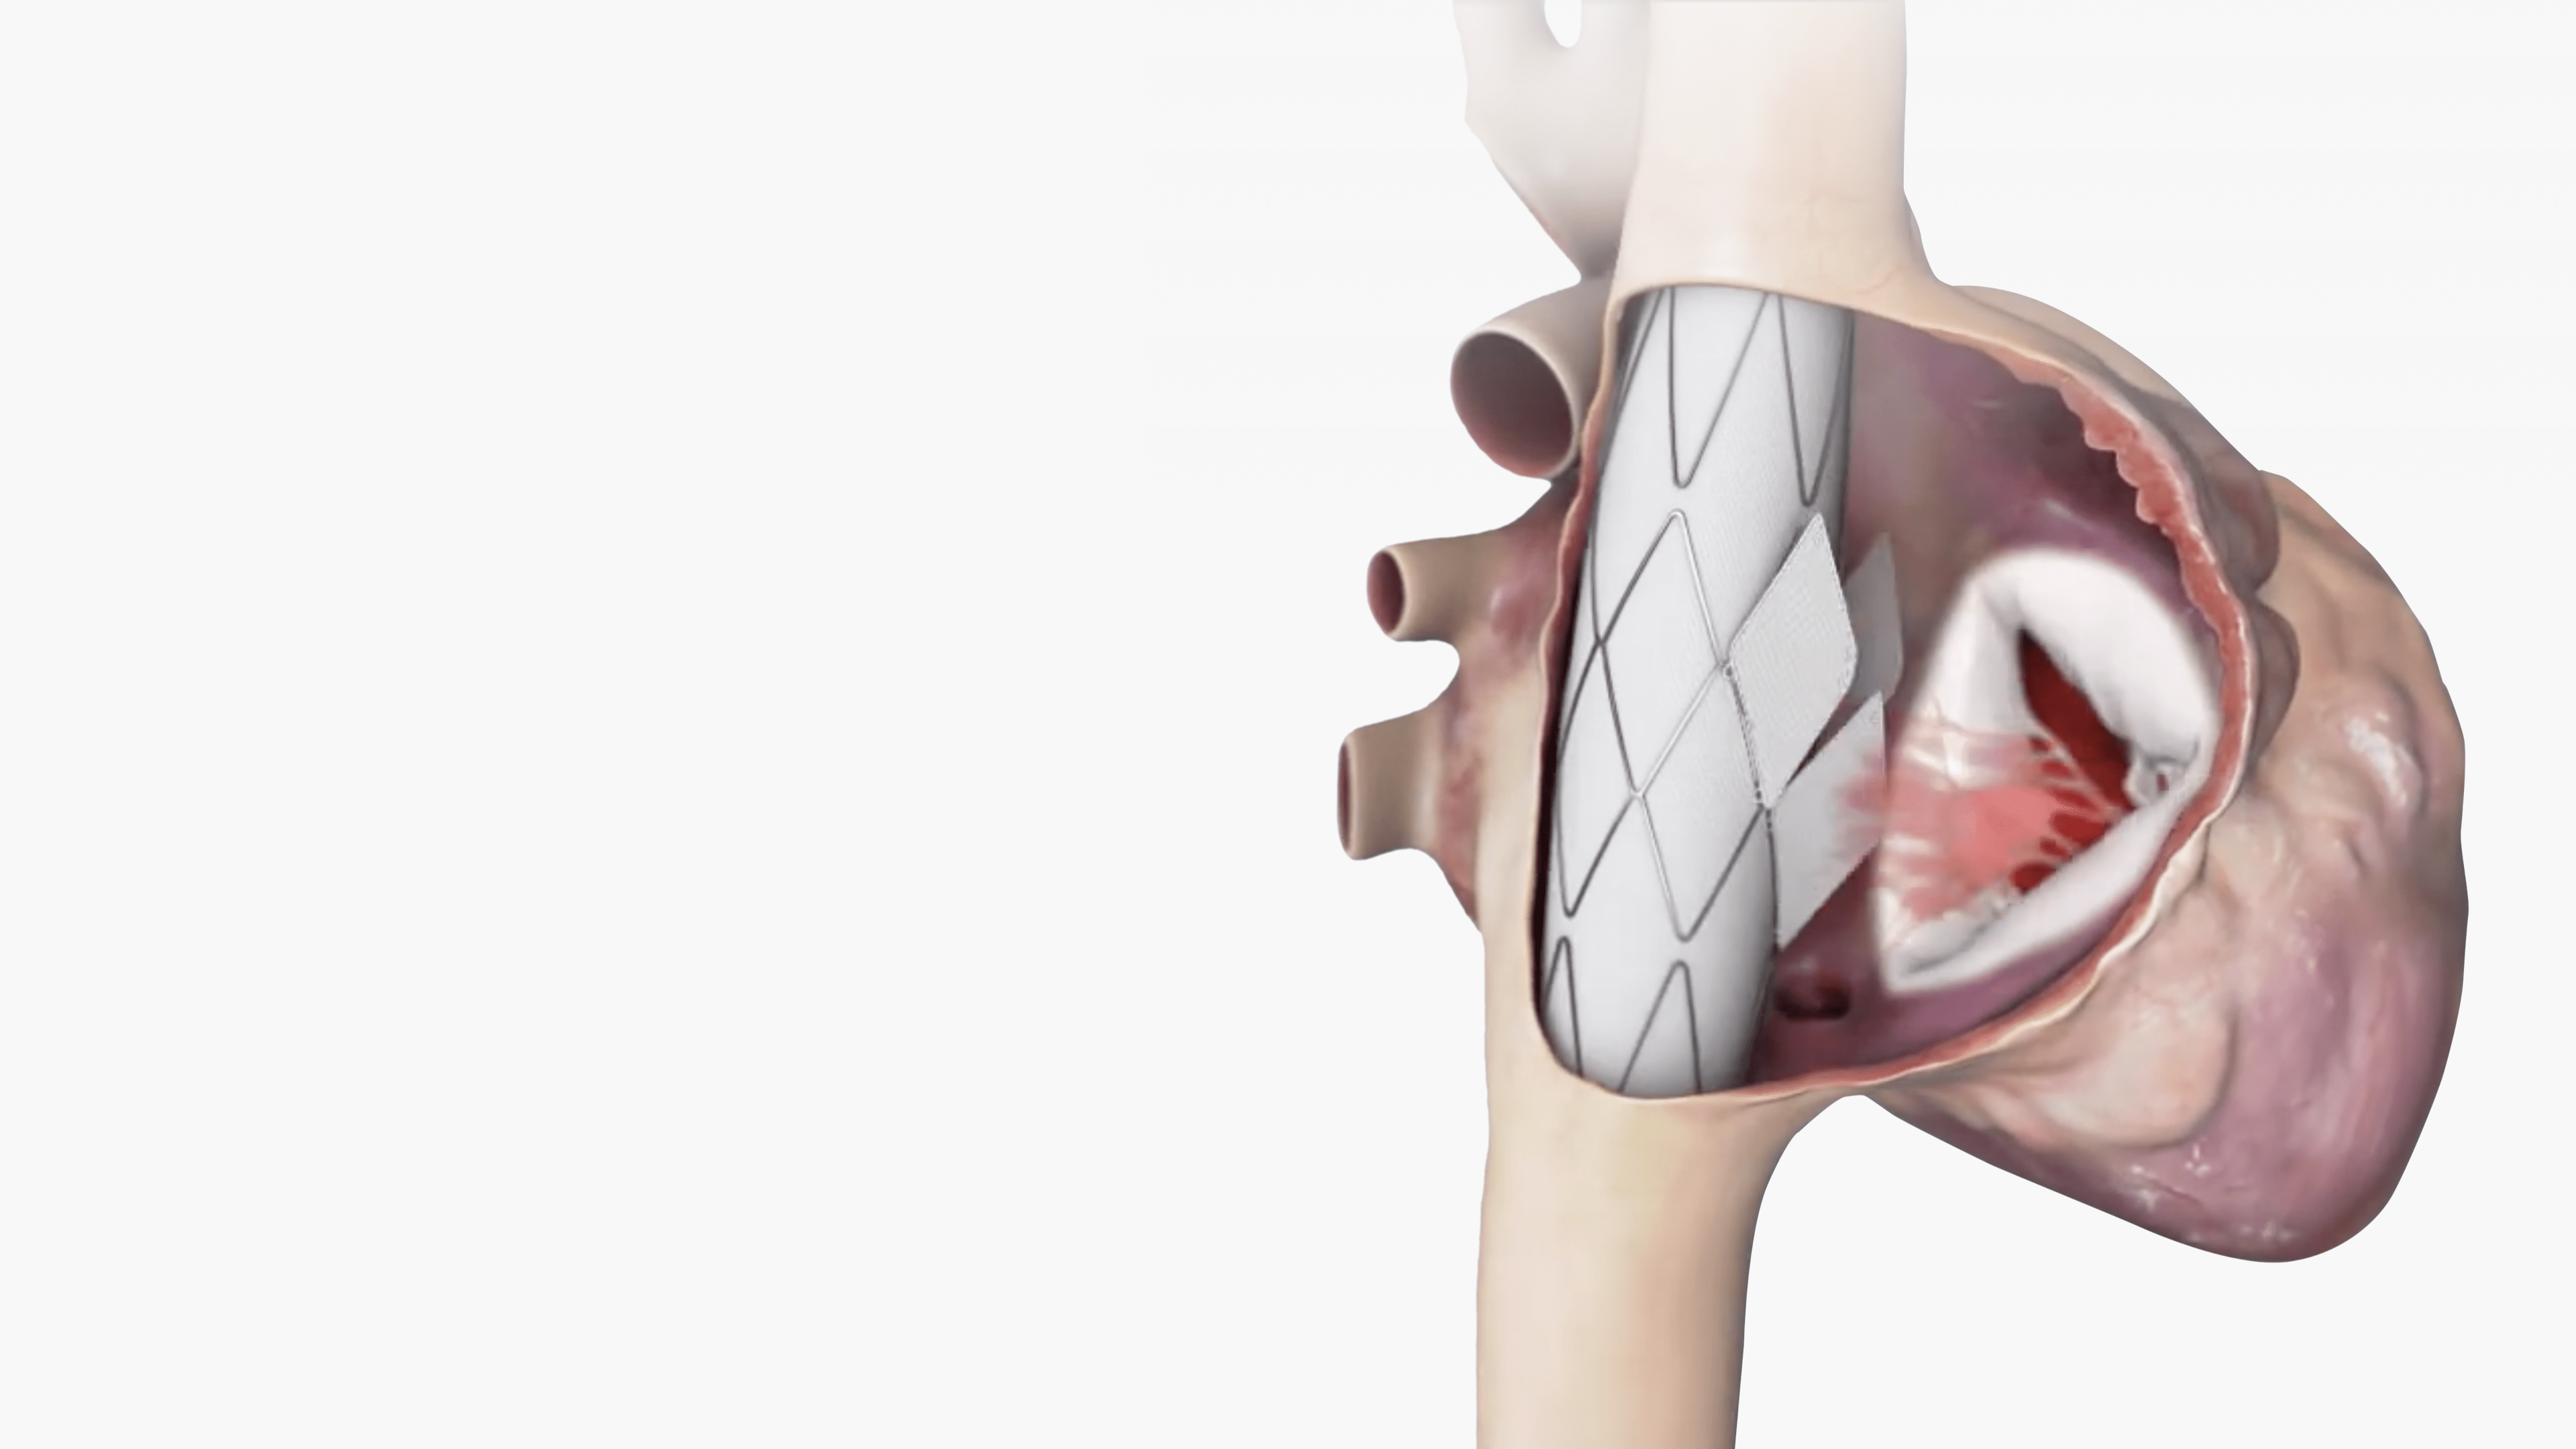

Trillium™ is meticulously crafted for the unique demands of the tricuspid valve environment.

This stent graft, featuring a valved wall, is designed to span the right atrium with secure fixation

in the Superior Vena Cava (SVC) and Inferior Vena Cava (IVC), leaving the native valve untouched.

Migration Resistant

A single device anchored to two

apposing anatomies (SVC & IVC),

provides reliable anchoring and full

migration resistance.

Large Flange Sealing Skirt

Creates a secure seal that fits a wide

range of anatomies, while allowing

the necessary hepatic vein inflow.